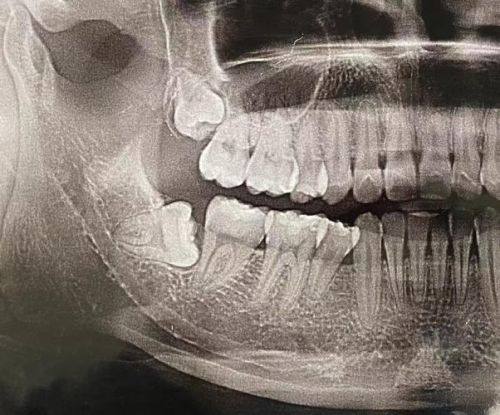

3. 设备精良:拥有芬兰数字化全景X光机、CBCT、口内扫描仪等,为精细诊疗提供支持。